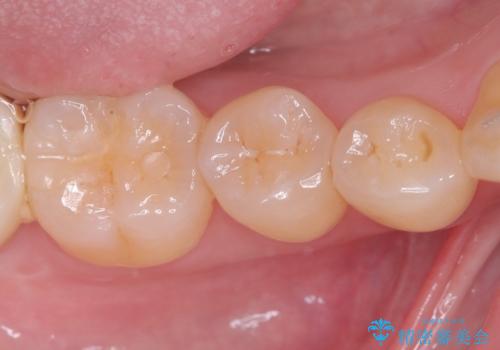

セラミックインレーによる虫歯治療

- 右下5の虫歯をセラミックインレーで修復しました。虫歯は進行することで歯に悪影響を及ぼし、放置するとさらなる問題を引き起こす可能性があります。再発のリスクをできるだけ回避するため、セラミックインレーを用いて治療を行いました。

装着する際にはラバーダムを使用しています。